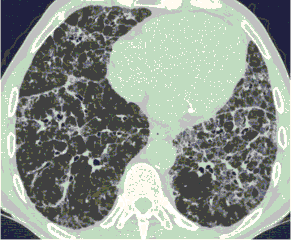

4.3. ЛУЧЕВАЯ ДИАГНОСТИКА COVID-19

Методы лучевой диагностики применяют для выявления COVID-19 пневмоний, их осложнений, дифференциальной диагностики с другими заболеваниями легких, а также для определения степени выраженности и динамики изменений, оценки эффективности проводимой терапии.

К методам лучевой диагностики патологии ОГК пациентов с предполагаемой/установленной COVID-19 пневмонией относят:

- Компьютерную томографию легких (КТ),

КТ имеет высокую чувствительность в выявлении изменений в легких, характерных для COVID-19. Применение КТ целесообразно для первичной оценки состояния ОГК у пациентов с тяжелыми прогрессирующими формами заболевания, а также для дифференциальной диагностики выявленных изменений и оценки динамики процесса. КТ позволяет выявить характерные изменения в легких у пациентов с COVID-19 еще до появления положительных лабораторных тестов на инфекцию с помощью МАНК. В то же время, КТ выявляет изменения легких у значительного числа пациентов с бессимптомной и легкой формами заболевания, которым не требуется госпитализация. Результаты КТ в этих случаях не влияют на тактику лечения и прогноз заболевания при наличии лабораторного подтверждения COVID-19. Поэтому массовое применение КТ для скрининга асимптомных и легких форм болезни не рекомендуется. При первичном обращении пациента с подозрением на COVID-19 рекомендуется назначать КТ только при наличии клинических и инструментальных признаков дыхательной недостаточности (SpO2 < 95%, ЧДД > 22).

3. Применение лучевых методов у пациентов с симптомами ОРВИ легкой степени тяжести и стабильном состоянии пациента, возможно только по конкретным клиническим показаниям, в том числе при наличии факторов риска, при условии достаточных технических и организационных возможностей. Методом выбора в этом случае является КТ легких по стандартному протоколу без внутривенного контрастирования или РГ при ограниченной доступности КТ. Использование УЗИ в этих случаях нецелесообразно. Применение КТ исследования в сроки ранее 3 - 5 дней с момента появления симптомов заболевания, а также при отсутствии клинических проявлений поражения бронхолегочной системы является нецелесообразным. Выполнение КТ целесообразно при наличии клинических и инструментальных признаков дыхательной недостаточности (SpO2 < 95%, ЧДД > 22), либо при дифференциальной диагностике с другим заболеванием.